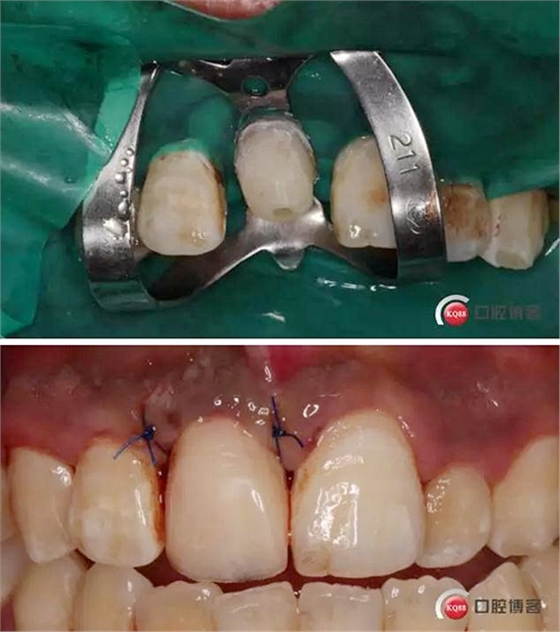

溝通后局麻下切齦,翻瓣,去骨,做冠延長。翻瓣后上橡皮障 去盡繼發(fā)齲,打樁堆核,暫冠修復(fù)引導(dǎo)牙齦成型。

術(shù)后牙片可以看出樁的長度有明顯增加。到達(dá)預(yù)備長度。術(shù)后齦緣高度與鄰牙一致